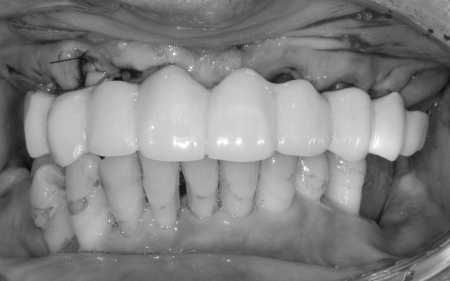

①上の歯7本、右下の奥歯2本を抜歯する。上あごには抜歯と同時に4本のインプラントを埋め、その上に10本分の仮歯を取り付けるオールオンフォーを行う。

インプラントの種類には、あごの骨と結合する力に優れたオステム社のETⅢを採用。インプラントが骨にしっかり定着するまでの間は、通常のインプラントよりも細い暫間インプラントを一時的に併用して仮歯を支える

②インプラントが安定したことを確認してから、仮歯を外して最終的な人工歯を装着する

最後に、残っている下の歯としっかりと噛み合っていることを確認し、治療を終了しました。